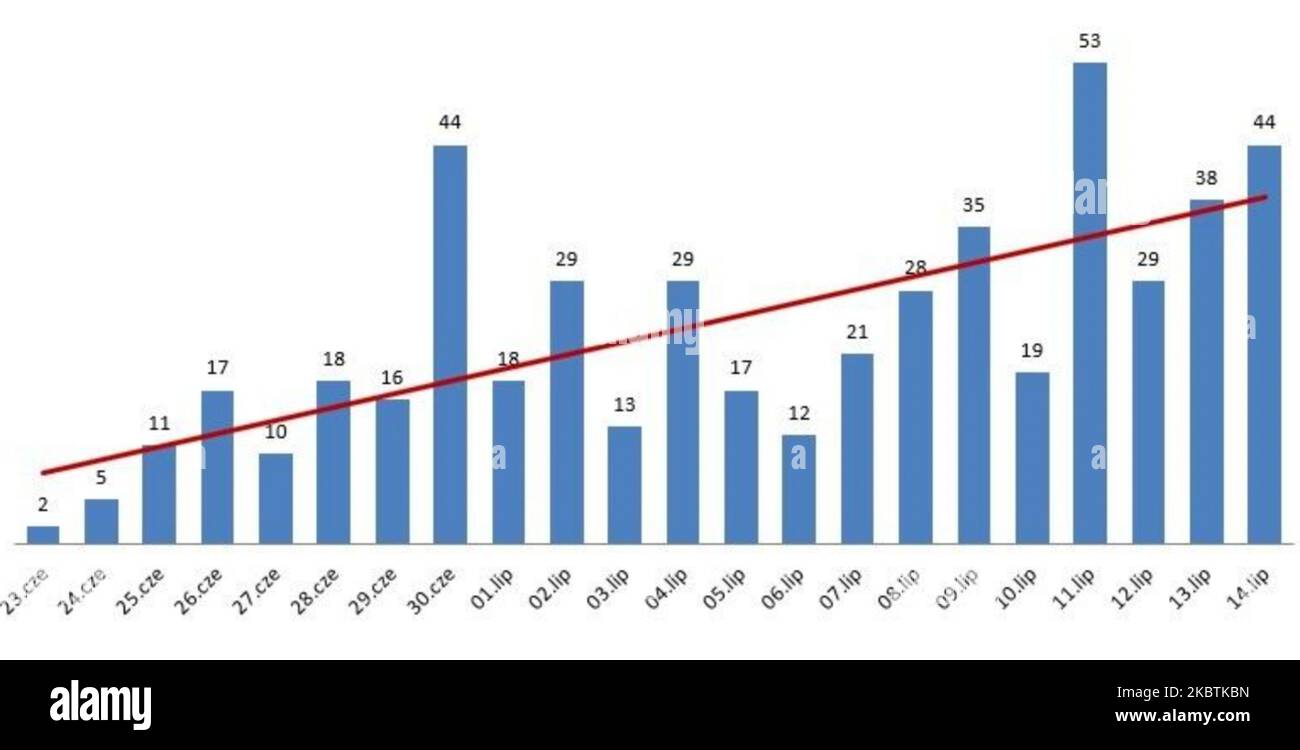

Un grafico che mostra i nuovi casi di coronavirus nella Voivodato della Polonia minore nelle ultime 3 settimane. La regione della Polonia minore è di nuovo in prima linea nell'infezione da coronavirus in Polonia. Il Ministero della Salute ha riferito oggi 267 nuovi casi (inclusi 44 casi nella regione della Polonia minore) e 12 morti, aumentando il numero totale a 38.457 persone infette, 1.588 morti e 27.756 guarite. La media mobile di 7 giorni dei nuovi casi di coronavirus varia tra 260 e 300 al giorno. Martedì 14 luglio 2020 a Cracovia, Polonia. (Foto di Artur Widak/NurPhoto) Foto Stockhttps://www.alamy.it/image-license-details/?v=1https://www.alamy.it/un-grafico-che-mostra-i-nuovi-casi-di-coronavirus-nella-voivodato-della-polonia-minore-nelle-ultime-3-settimane-la-regione-della-polonia-minore-e-di-nuovo-in-prima-linea-nell-infezione-da-coronavirus-in-polonia-il-ministero-della-salute-ha-riferito-oggi-267-nuovi-casi-inclusi-44-casi-nella-regione-della-polonia-minore-e-12-morti-aumentando-il-numero-totale-a-38457-persone-infette-1588-morti-e-27756-guarite-la-media-mobile-di-7-giorni-dei-nuovi-casi-di-coronavirus-varia-tra-260-e-300-al-giorno-martedi-14-luglio-2020-a-cracovia-polonia-foto-di-artur-widak-nurphoto-image489193593.html

Un grafico che mostra i nuovi casi di coronavirus nella Voivodato della Polonia minore nelle ultime 3 settimane. La regione della Polonia minore è di nuovo in prima linea nell'infezione da coronavirus in Polonia. Il Ministero della Salute ha riferito oggi 267 nuovi casi (inclusi 44 casi nella regione della Polonia minore) e 12 morti, aumentando il numero totale a 38.457 persone infette, 1.588 morti e 27.756 guarite. La media mobile di 7 giorni dei nuovi casi di coronavirus varia tra 260 e 300 al giorno. Martedì 14 luglio 2020 a Cracovia, Polonia. (Foto di Artur Widak/NurPhoto) Foto Stockhttps://www.alamy.it/image-license-details/?v=1https://www.alamy.it/un-grafico-che-mostra-i-nuovi-casi-di-coronavirus-nella-voivodato-della-polonia-minore-nelle-ultime-3-settimane-la-regione-della-polonia-minore-e-di-nuovo-in-prima-linea-nell-infezione-da-coronavirus-in-polonia-il-ministero-della-salute-ha-riferito-oggi-267-nuovi-casi-inclusi-44-casi-nella-regione-della-polonia-minore-e-12-morti-aumentando-il-numero-totale-a-38457-persone-infette-1588-morti-e-27756-guarite-la-media-mobile-di-7-giorni-dei-nuovi-casi-di-coronavirus-varia-tra-260-e-300-al-giorno-martedi-14-luglio-2020-a-cracovia-polonia-foto-di-artur-widak-nurphoto-image489193593.htmlRM2KBTKBN–Un grafico che mostra i nuovi casi di coronavirus nella Voivodato della Polonia minore nelle ultime 3 settimane. La regione della Polonia minore è di nuovo in prima linea nell'infezione da coronavirus in Polonia. Il Ministero della Salute ha riferito oggi 267 nuovi casi (inclusi 44 casi nella regione della Polonia minore) e 12 morti, aumentando il numero totale a 38.457 persone infette, 1.588 morti e 27.756 guarite. La media mobile di 7 giorni dei nuovi casi di coronavirus varia tra 260 e 300 al giorno. Martedì 14 luglio 2020 a Cracovia, Polonia. (Foto di Artur Widak/NurPhoto)